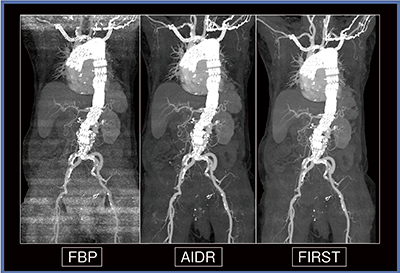

図1は,EVAR術前の体幹部造影CTで,80kV,造影剤量60%で撮影し,FBP,AIDR,FIRSTで再構成を行った。左上肢から注入した造影剤によって,FBP,AIDRでは周囲に強いアーチファクトが出ているが,FIRSTでは造影剤(↑)だけでなく,開胸術後の胸骨の金属アーチファクト(▼)も軽減され,周囲の構造も見やすくなっている。MIP画像(図2)でも,FIRSTでは造影剤のアーチファクトだけでなく肩関節によるアーチファクトも軽減されている。

図2 症例1のMIP画像

FIRSTでは上肢の造影剤や肩のアーチファクトが低減されている。